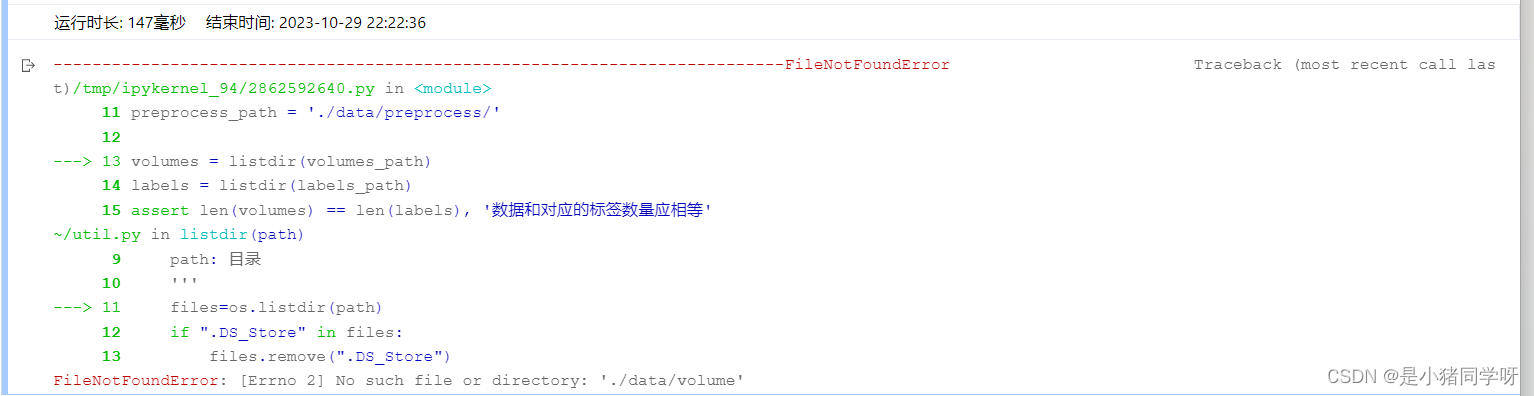

经过测试,肝脏和肝脏肿瘤分割系统的各项功能都能够正常工作,满足用户需求。在白盒测试方面,覆盖了网络结构、特征提取、特征映射、损失函数等方面,没有发现明显的问题。在黑盒测试方面,采用了等价类划分、边界值分析、因果图和错误推测等方法,测试结果表明系统的各项指标均符合要求,没有发现明显的问题。

本次测试结果表明,肝脏和肝脏肿瘤分割系统的各项功能都能够正常工作,满足用户需求。在白盒测试和黑盒测试方面,测试覆盖了网络结构、特征提取、特征映射、损失函数、上传CT影像、查看分割结果、后处理、性能评估、恢复测试、安全测试、强度测试和性能测试等方面,测试结果表明系统的各项指标均符合要求,没有发现明显的问题。